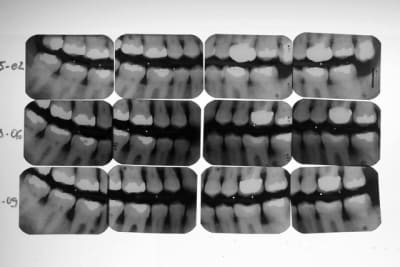

Le patient ne sait absolument pas quand son inocclusion a commencé. D’ailleurs il ne s’en était pas aperçu. J’ai mis des clichés BW de ce patient à différentes dates ( un peu floue : désolé). J’avoue ne m’être intéressé uniquement à la paro de ce patient lors des dernières consultations.

PS1 La ccm sur 26 a été réalisée en occlusion en 2005

PS2 Les dents, sur les secteurs postérieurs, se sont considérablement écartées sans doute due à la pulsion linguale.